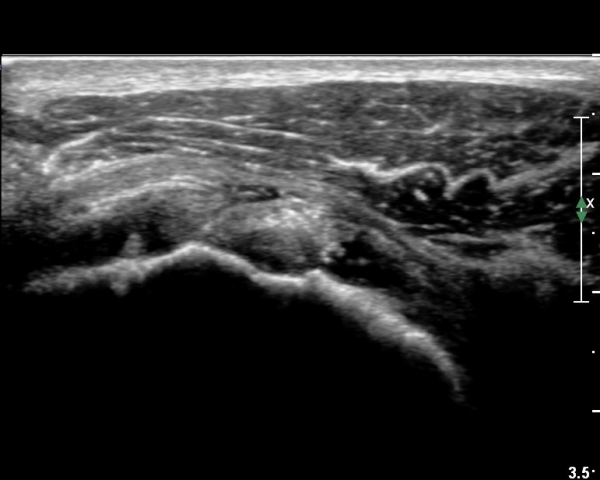

ÃÊÀ½ÆÄ ¼Ò°ß :  È¸Àü±Ù°³°£°Ý °Ë»ó»ó ±Ø»ê°ÇÀº Á¤»ó¼Ò°ßÀ» º¸À̳ª °ß°©ÇϱٰÇÀº Àú¿¡ÄÚ ¿¬°á¼º ¼Ò½ÇÀÌ

º¸¿© °ß°©ÇÏ±Ù°Ç ÆÄ¿­ÀÌ ÃßÁ¤µÈ´Ù(»çÁø 1). ŽÃËÀÚ¸¦ ¾à°£ ¾Æ·¡·Î À̵¿ÇÑ ÈÄ

ÆÈÀ» ¿ÜȸÀüÇϸ鼭 °üÂûÇÏ´Ï °ß°©ÇÏ±Ù°Ç ÆÄ¿­ÀÌ ¶Ñ·ÈÇÔ(»çÁø 2, 3).